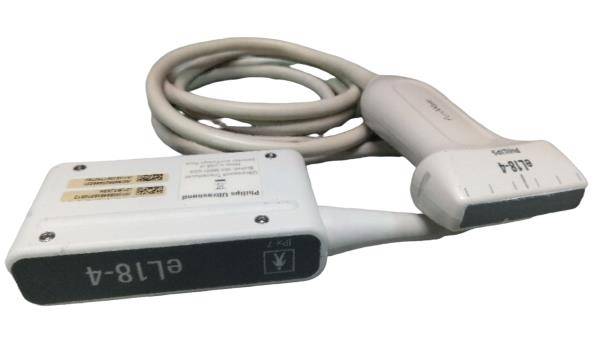

PHILIPS S5-1 SECTOR ARRAY ULTRASOUND PROBE

The Philips S5-1 Sector Array Ultrasound Probe is a high-performance imaging transducer designed for a range of clinical applications, including abdominal, cardiac, and obstetric/gynecological imaging. With a frequency range of 1-5 MHz, this probe offers excellent tissue penetration for deeper imaging, while maintaining high-resolution images for accurate diagnostics. The sector array design enables the probe to capture detailed images from a small footprint, making it ideal for patients with challenging body types or when accessing confined anatomical areas.

The Philips S5-1 probe is widely used for echocardiograms and other cardiovascular applications, as well as abdominal and obstetric exams. Known for its durability and reliability, it is compatible with Philips ultrasound systems and supports a variety of imaging modalities such as Doppler and 2D imaging. The S5-1 is designed for ease of use, providing clinicians with clear, real-time images to guide accurate diagnoses and treatment decisions.